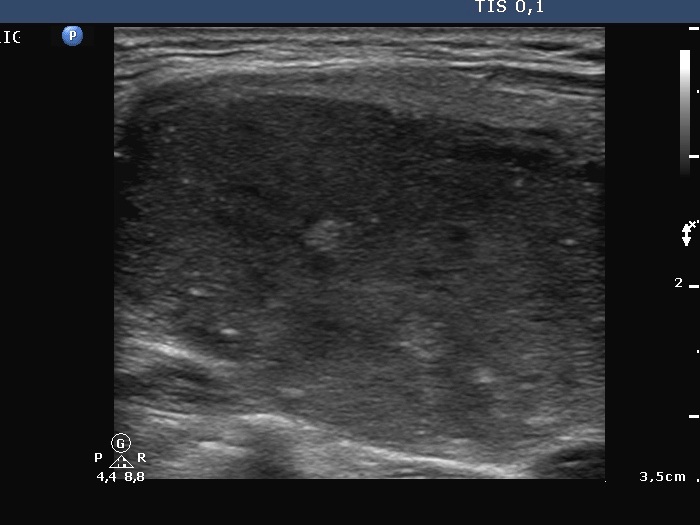

First examination (first row of sonographic images):

Clinical presentation: A 33-year-old woman was referred for evaluation of typical complaints suggesting hyperthyroidism.

Palpation: Both lobes were enlarged.

Functional state: hyperthyroidism (TSH undetectable, FT4 42.2 pM/L, FT3 above 46 pM/L).

Ultrasonography. The thyroid was diffusely hypoechogenic. The vascularization was increased. The left thyroid was significantly more inhomogeneous than the right lobe. Compare the first two index pictures in the first row with the third and fourth one, right and left lobe, respectively.